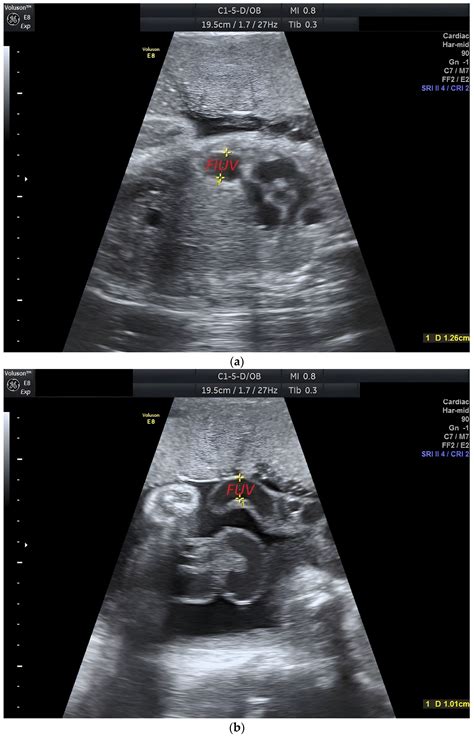

The identification of a Persistent Right Umbilical Vein is primarily achieved through high-resolution fetal ultrasonography. During the mid-trimester scan (typically between 18 and 22 weeks), sonographers examine the fetal abdomen to ensure that the umbilical vein is entering the liver correctly. When a PRUV is present, the sonographer will observe the following characteristic signs:

• The umbilical vein courses to the right side of the gallbladder, rather than the left.

• The vessel takes a slightly different anatomical path toward the portal system.

• The color Doppler ultrasound shows a change in the direction of the vascular flow compared to the expected norm.

Because these findings can be subtle, ultrasound technicians and maternal-fetal medicine specialists are trained to look for these specific markers when the abdominal anatomy does not appear completely symmetrical. Once identified, the radiologist or obstetrician will conduct a detailed survey of the entire fetus to rule out any associated structural abnormalities.